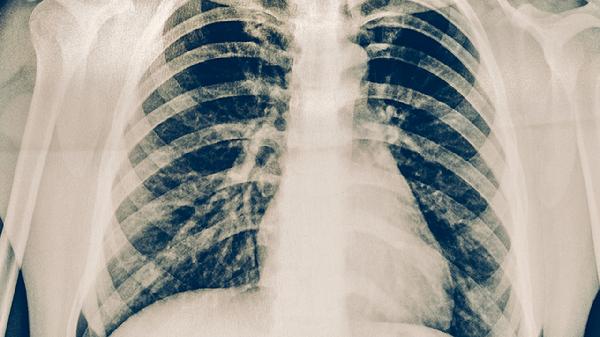

胸平扫CT可以排除肺癌吗

胸平扫CT通常不能完全排除肺癌,但可以作为初步筛查手段。肺癌诊断需结合病理活检、肿瘤标志物检测等综合评估。

胸平扫CT能发现肺部结节或肿块,对早期微小病灶的敏感性有限。部分磨玻璃样结节、微小结节可能因分辨率不足被遗漏。炎症、结核等良性病变也可能在影像上呈现类似肺癌的表现,导致假阳性结果。对于高风险人群,低剂量螺旋CT的检出率更高,但仍需进一步检查确认。